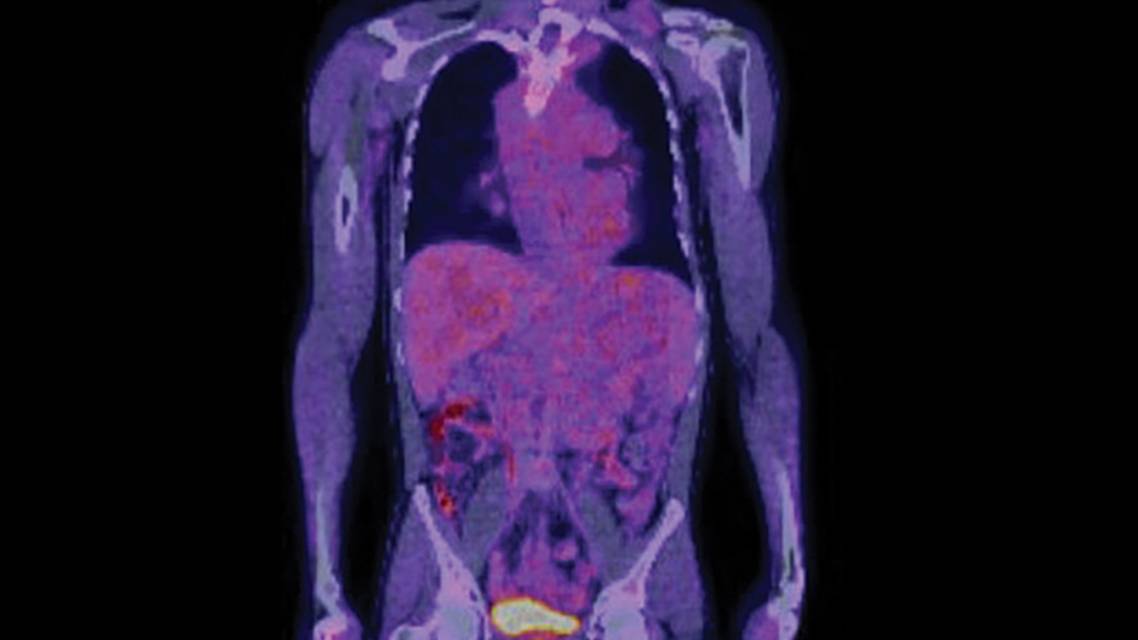

Diagnostic evaluation is tailored to the individual, taking age and clinical manifestations into consideration. Individuals with NF1 are recommended to undergo regular comprehensive ophthalmologic examinations, have close follow-up with a dermatologist, and be evaluated for clinical signs of pheochromocytoma with regular blood pressure checks. Other diagnostic testing is obtained on a case-by-case basis; for example, in adults, MRI scans of the brain and orbits are obtained in case of clinical symptoms that could be consistent with a glioma or other structural abnormality, and [¹⁸F]fluorodeoxyglucose positron emission tomography (FDG-PET) scans are obtained to evaluate a worrisome or clinically changing PN concerning for malignant transformation, but neither scan would be required without associated clinical concern (Figures 1, 2).

Figure 1. Imaging results demonstrating plexiform neurofibroma. T2 short tau inversion recovery sequence of coronal MRI of the neck, chest, and abdomen demonstrates extensive plexiform neurofibroma infiltration along the left neck and left side of the abdomen, and extending into the pelvis (A). On [¹⁸F]fluorodeoxyglucose positron emission tomography/CT in the same patient, a similar coronal slice shows only mild [¹⁸F]fluorodeoxyglucose avidity (maximum standardized uptake value 3.3) of the plexiform neurofibroma in the neck (B).